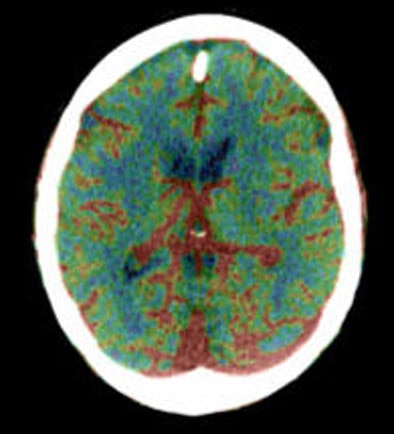

| Top to bottom: Perfusion CT images overlaid on CT source images of a 73-year-old male patient. The patient was scanned 30 minutes after the sudden onset of right hemiparesis with an NIHSS of 20. Above, cerebral blood flow (CBF) map shows a blue-color area of low CBF (range: 0-12 mL/100g/min) in the basal ganglia on the left side, which corresponds to the irreversibly infarcted tissue. Note the peripheral area displayed as green, which corresponds to the penumbra region (range: 12-24 mL/100 g/min). In the image below, cerebral blood volume (CBV) map does not demonstrate a clear delineation of the infarcted region in comparison with the CBF map. In the bottom image, mean transit time (MTT) map shows a slightly larger abnormality than seen on the CBF map. Images courtesy of Dr. Sotirios Bisdas. |